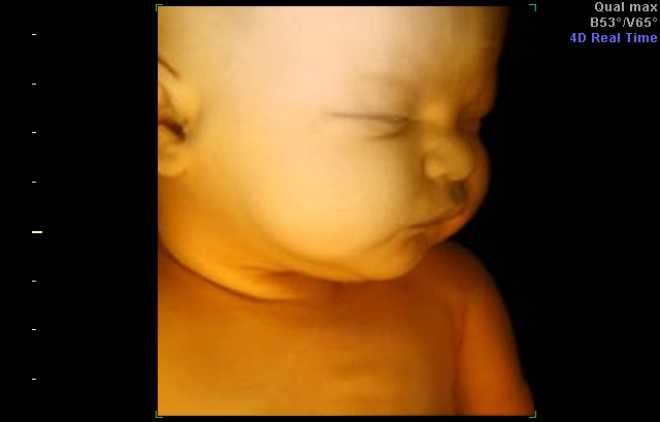

4D

4Д позволяет не только увидеть, но и услышать ребенка, его сердцебиение, звуки. На монитор поступает не изображение, а видео. Обследование можно записать на диск или на другой накопитель, получив на память фильм о внутриутробной жизни ребенка. Назначается с 15 по 33 неделю беременности, длительность обследования – от 1 часа. 4D не наносит вреда плоду, сила, интенсивность ультразвуковой волны приравниваются к обычному ультразвуковому исследованию.